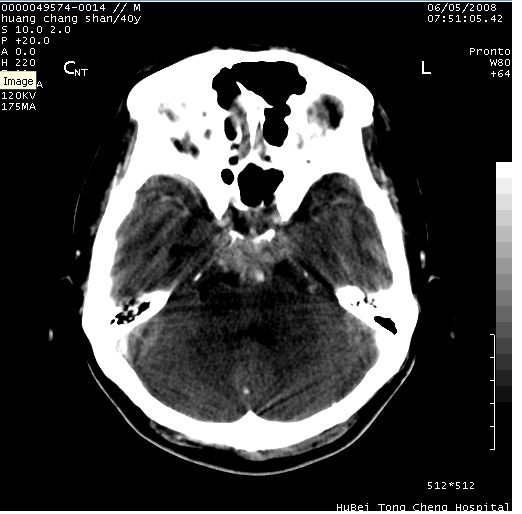

患者 m,40y。头痛,视力模糊,多饮多尿,性欲减退半年余。

行ct平扫+增强,图象如下:

肿瘤强化明显、鞍部骨质结构未见增大、破坏,考虑脑膜瘤可能性大

鞍背无破坏和明显受压,病变明显均匀强化,边界清晰。鞍上区脑膜瘤可能性大,不除外生殖细胞瘤。

鞍上池肿瘤,鞍背及垂体窝形态变化不明显,病灶强化密度均匀且高度强化,考虑实性颅咽管瘤、生殖细胞瘤及脑膜瘤可能。

结合临床考虑鞍上生殖细胞瘤可能性大于脑膜瘤(增强未见脑膜围征),建议结合冠状位扫描看病灶起源及垂体窝、鞍底情况。垂体窝内未见明显软组织密度影,垂体窝未见扩大,暂不考虑垂体瘤;病灶较大,未见囊变及钙化,颅咽管瘤不支持。期待结果!

2、ct表现:肿瘤呈类圆形,均匀略高密度,无囊变,无钙化。侧脑室有扩大。

4、鉴别诊断:脑膜瘤,瘤体内点状钙化最具特征性,常位于鞍结节。颅咽管瘤,蛋壳样钙化,常有囊变。动脉瘤,位于鞍旁,强化与动脉一致。有时尚需与发生于鞍区的生殖细胞瘤鉴别,生殖细胞瘤钙化亦较常见。